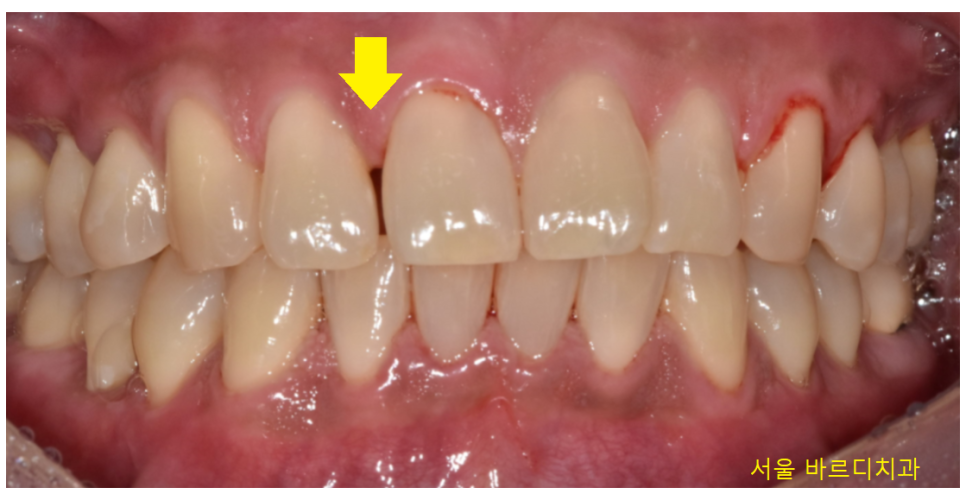

고덕 그라시움 치과 방문해주신 환자분의 경우에도

미세하지만 앞니 사이 공간이 있었습니다.

작은 틈새이지만

공간이 있어서 떼우고 싶다고 하셨습니다.

아무래도 반대편 치아의 경우

붙어있어서 더 비교가 되셨나봐요~

23.01.30

반대편 치아만 해도 잘 붙어있는데

유독 윗니 앞 부분 치아만 틈이 있네요~